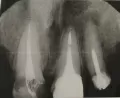

Должны были поставить коронку на зуб в платной клинике, но обнаружили, что на нижнем зубе, снимка которого нет, есть воспаление и он подлежит удалению. Затем предложили альтернативу заложить кальций. Все сделали, заодно запломбировали 4-ый канал зуба, который представлен на снимке. Через два дня на него должны были ставить временную коронку, но он стал крайне чувствительным. Мы не смогли установить потому что не подействовало даже три укола анестезии. Мне сказали, что боль может быть и это нормально. Назначили придти через дня 4. За эти дни боль не ушла, а скорее увеличилась. Стала болеть надкостница.

Сегодня я не выдержала и поехала в дежурную стоматологию. Мне сделали снимок и сказали, что он подлежит удалению, хотя мне об этом в моей платной стоматологии ничего не сказали. Болит десна, когда нажимали, сказали, что на то, что простудила это не похоже. Врач делала снимки и до и после лечения каналов и ничего не сказала.

Действительно зуб проблемный.

Корневые каналы не до конца запломбированы, на верхушке корня очаг воспаления.

Врач поторопился, но в любом случае коронку на него нельзя было одевать, он очень ненадежный.